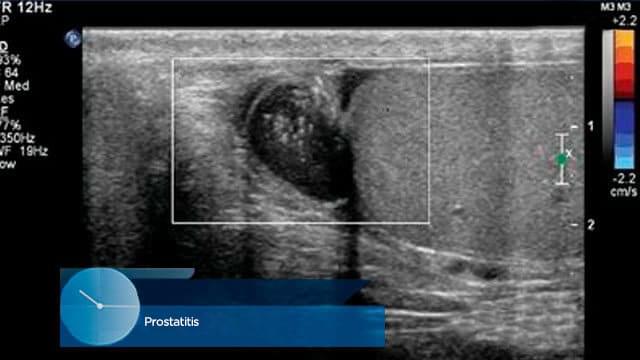

Za pravilno oceno obsega težave in razumevanje, da je ignoriranje težav s prostato in sečil ena od usodnih napak moških, pokažem nekaj slik.

Matija Markuš: Poglejmo zaslon!

1. Rak prostate pri 41-letnem moškem. Umrl je. Sta osirotela 2 majhna otroka.

2. Hud prostatitis. Potrebna je bila nujna amputacija žleze. Moški je postal impotenten.

3. Adenokarcinom prostate. Pravočasno so ga prepoznali. Rak se ni razvil.

4. Odpoved ledvic zaradi prisotnosti gnojnega povzročitelja v prostati